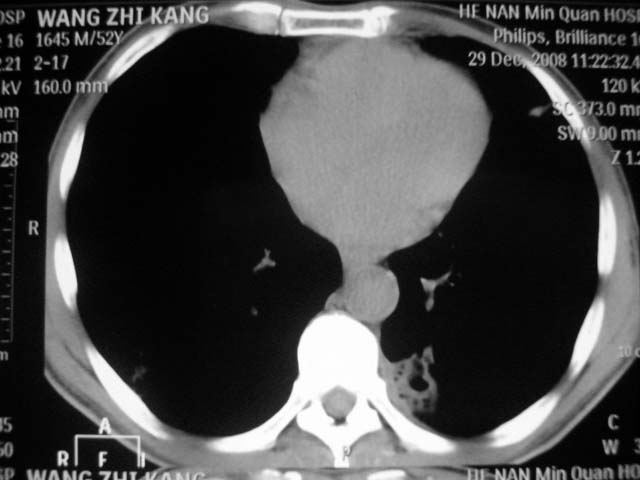

男,52岁,发热2月,糖尿病史。

抗结核治疗irpz方案,血糖未治疗,空腹15.9左右。症状无好转,左胸痛。

复查ct

2、双肺见多发片状及结节状高密度影,大多数病灶中心均见“空泡征”。

3、纵隔内淋巴结肿大。

结果:两肺继发性肺结核并曲霉菌感染。